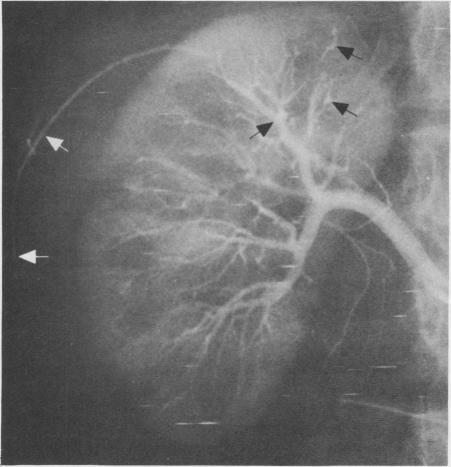

A casual relationship between von Recklinghausen's disease, or neurofibromatosis, and arteriolar abnormalities has been reported in the European literature. A patient was seen who had biopsy-proved neurofibromatosis and renovascular hypertension and retroperitoneal bleeding. An arteriographic study showed multiple small aneurysms throughout the coeliac axis, the superior mesenteric artery and in several small intrarenal vessels. Renal vein renin levels were elevated particularly in the right renal vein, supporting the diagnosis of renovascular hypertension. Both the aneurysms seen in angiographic studies and the retroperitoneal hemorrhage are probably vascular manifestations of von Recklinghausen's disease. Support for this conclusion is enhanced by the absence of clinical, laboratory or histologic data supporting the only tenable differential diagnosis, periarteritis nodosa.

欧洲文献报道了冯雷克林霍增氏病(即神经纤维瘤病)与小动脉异常之间的偶然关系。有一位经活检证实患有神经纤维瘤病且伴有肾血管性高血压和腹膜后出血的患者。血管造影研究显示,在整个腹腔动脉、肠系膜上动脉以及数条肾内小血管中存在多个小动脉瘤。肾静脉肾素水平升高,尤其是右肾静脉,这支持了肾血管性高血压的诊断。血管造影研究中所见的动脉瘤和腹膜后出血可能都是冯雷克林霍增氏病所致的血管表现。由于缺乏支持唯一合理鉴别诊断——结节性多动脉炎的临床、实验室或组织学数据,这一结论得到了进一步支持。